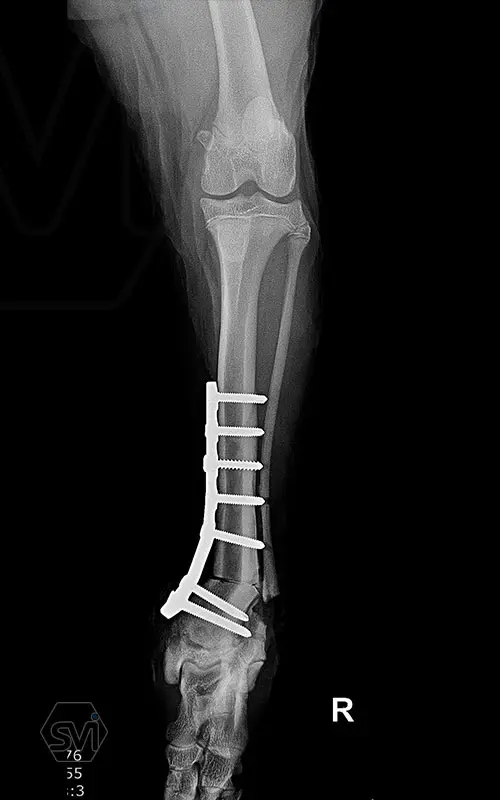

Multifunctional symmetrical long polyaxial locking plate - designed for the treatment of fractures close to joints

A special member of the polyaxial locking plate family is the multifunctional long plate, which is an extended version of the well-known symmetrical TPLO plate, with a 5-3 hole distribution. The plate also received a DCP hole to be able to create compression, and there is a mini-hole on the head end to facilitate the placement of the temporarily used K-nail. The burrs on the side facing the bone surface are intended to reduce the contact surface between the plate and the bone (limited contact).

The plate is a member of the large polyaxial locking family, suitable for 2.7-3.5-4.0 mm screws. We recommend it for fixaton of fractures close to joints, wedge osteotomies with axis correction (closing and opening), or for CWTO operations.